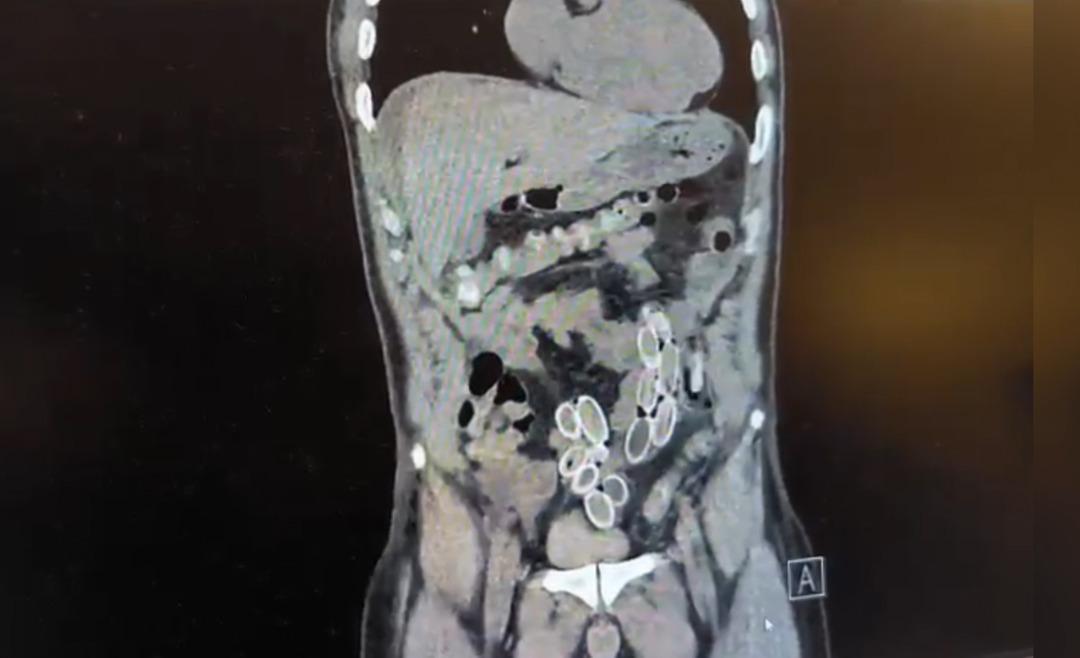

İhbar üzerine çalışma başlatan Beşiktaş Asayiş Büro Amirliği ekipleri, doktorlarla görüşme gerçekleştirdi. Doktorların değerlendirmesi sonrası ameliyata alınan Cüneyt Ç.’nin bağırsaklarından, toplam ağırlığı 259,7 gram olduğu öğrenilen 49 esrar macunu çıkarıldı. Şüpheliye ait 1 adet cep telefonu da hastane yetkilileri tarafından polis ekiplerine teslim edildi.